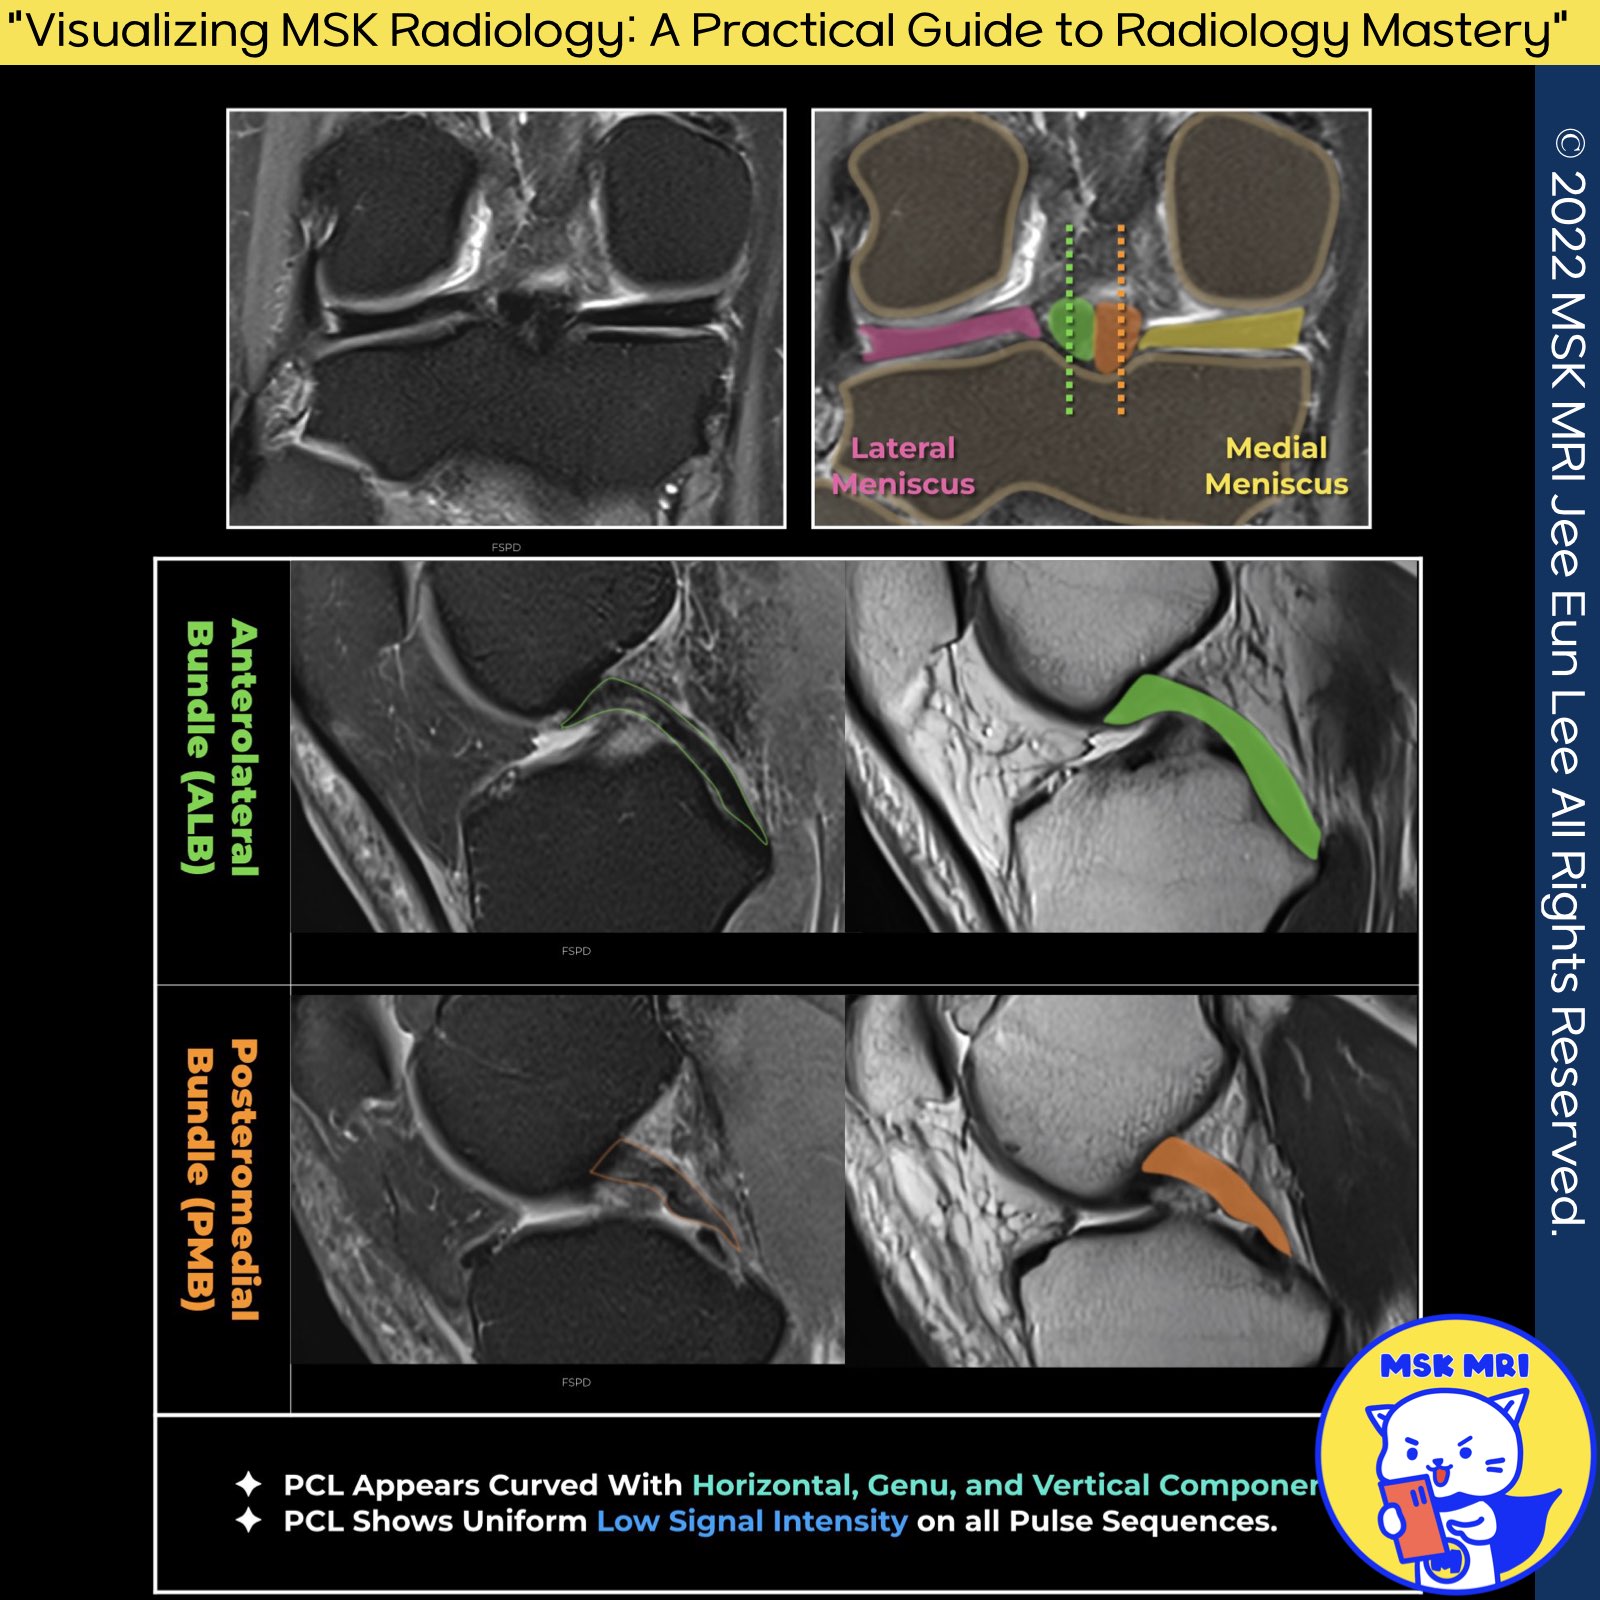

🔴 Anatomy of the PCL on Sagittal Images 🔴

1️⃣ Sagittal Plane Overview

➡️ The Posterior Cruciate Ligament in the sagittal plane displays a curved form, consisting of horizontal proximal, genu, and vertical distal components.

2️⃣ Anterolateral Bundle Characteristics

➡️ The AL bundle, larger at the midsubstance, is distinguished by the positioning of its femoral insertions. The stronger ALB originates anteriorly from the lateral margin of the medial femoral condyle, ahead of the PMB's origin.

➡️ Uniformity and Signal Intensity

- Uniform Low Signal Intensity: The PCL exhibits uniform low signal intensity across all pulse sequences.

- Increased Signal at the Genu: Slight increase in signal intensity may occur at the genu on short TE pulse sequences, attributed to the magic angle phenomenon.

- Differentiation from Partial Tear: A partial tear can be distinguished by the presence of corresponding low signal intensity on long-echo-time images and an anteroposterior thickness of the ligament measuring less than 6 mm.